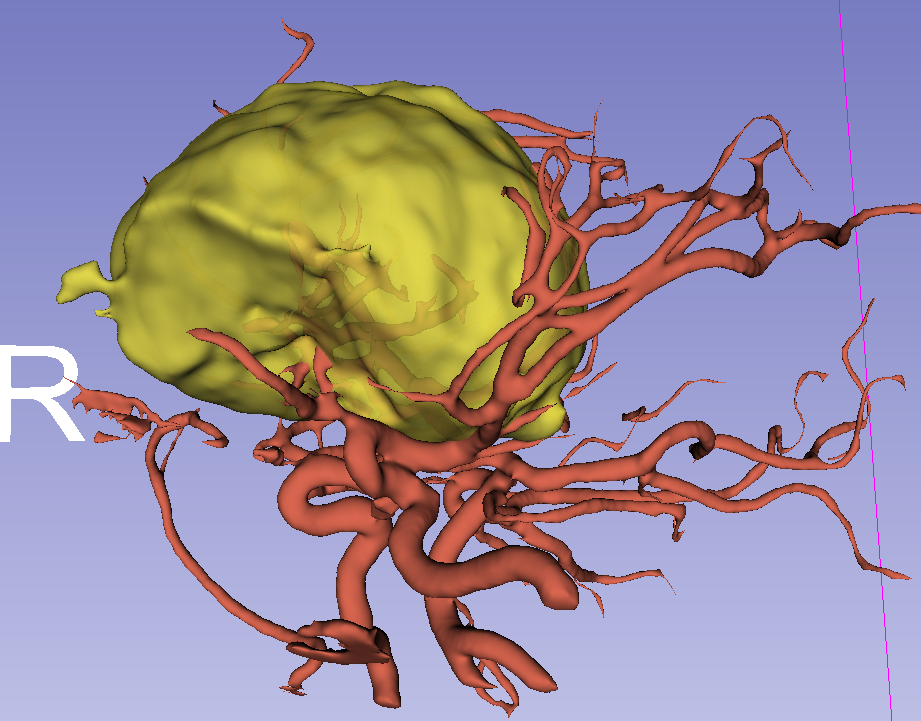

前颅窝底脑膜瘤常起源于前颅底筛骨筛板处的硬膜,瘤体多为双侧生长,少数为偏侧生长,女性稍多于男性。肿瘤可累及鸡冠和蝶骨平台的任何区域,是前颅窝肿瘤中最多见的一种。因为肿瘤位于前颅窝底,额叶在功能上属于“哑区”,患者就诊发现肿瘤时瘤体多已巨大。主要症状可有颅内压增高症状、视力减退、癫痫以及精神症状等。该患者主因“左眼失明10个月,头痛3个月”就诊。术中采用双额冠状开颅,左侧为主,由于肿瘤体积巨大,术中切除少许薄层额叶脑组织,边离断基底、边瘤内减压,分块切除肿瘤,最终探查肿瘤基底主要位于鸡冠、筛板、蝶骨平台、鞍结节、前床突处硬膜,术中见肿瘤供血主要来源于前颅窝底硬膜及大脑前动脉分支,术中仔细辨认供血动脉、过路血管,大脑前动脉及其分支保护完好,术中见视神经、视交叉受压明显,尤其是左侧视神经已缺血苍白,最终达Simpson II级切除。术者体会,该患者术前行多模态重建,可见瘤表数条粗大的静脉,术中切莫过早离断肿瘤的引流静脉,以防因引流不畅致瘤体肿胀出血;术前行多模态重建,利于鉴别供血动脉、过路血管,早期离断供血动脉更利于肿瘤切除;该类肿瘤基底一般较为广泛,不能盲目离断基底,尤其是近鞍结节处,可以于中线处离断基底,进入第一间隙后向两侧探查并保护视神经,待充分缩小瘤体看清楚毗邻的血管神经后再将其完全切除;术毕做好多层颅底重建以防脑脊液漏。另外,该患者术前左眼失明已达10个月,术后第1天即有光感,术后1月复查左眼视力可达50cm内数指,这在临床中非常少见,对于此类病人,不要轻易放弃挽救视力的任何机会。